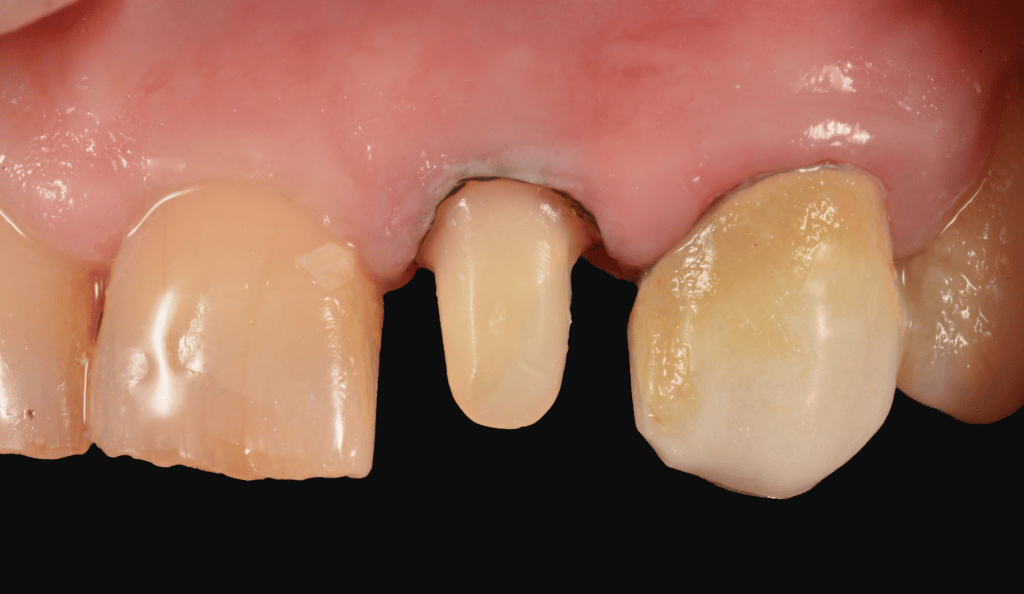

The preparation starts with calibrated depth grooves following the Kuwata inclined planes. To increase the precision in this phase, the depth of bur grovees are marked with a pencil and subsequently prepared.

A final champfer preparation is obtained with a subgingival margin of 0.5mm.

During the prep great attention is given to soft tissues.

With a 000 retraction cord the prep is finished slightly under the sulcus.

No bleeding is present and an immediate, final impression can be obtained using single phase putty and light Polyether impression material.

prep with depth grooves

prep finishing

final impression